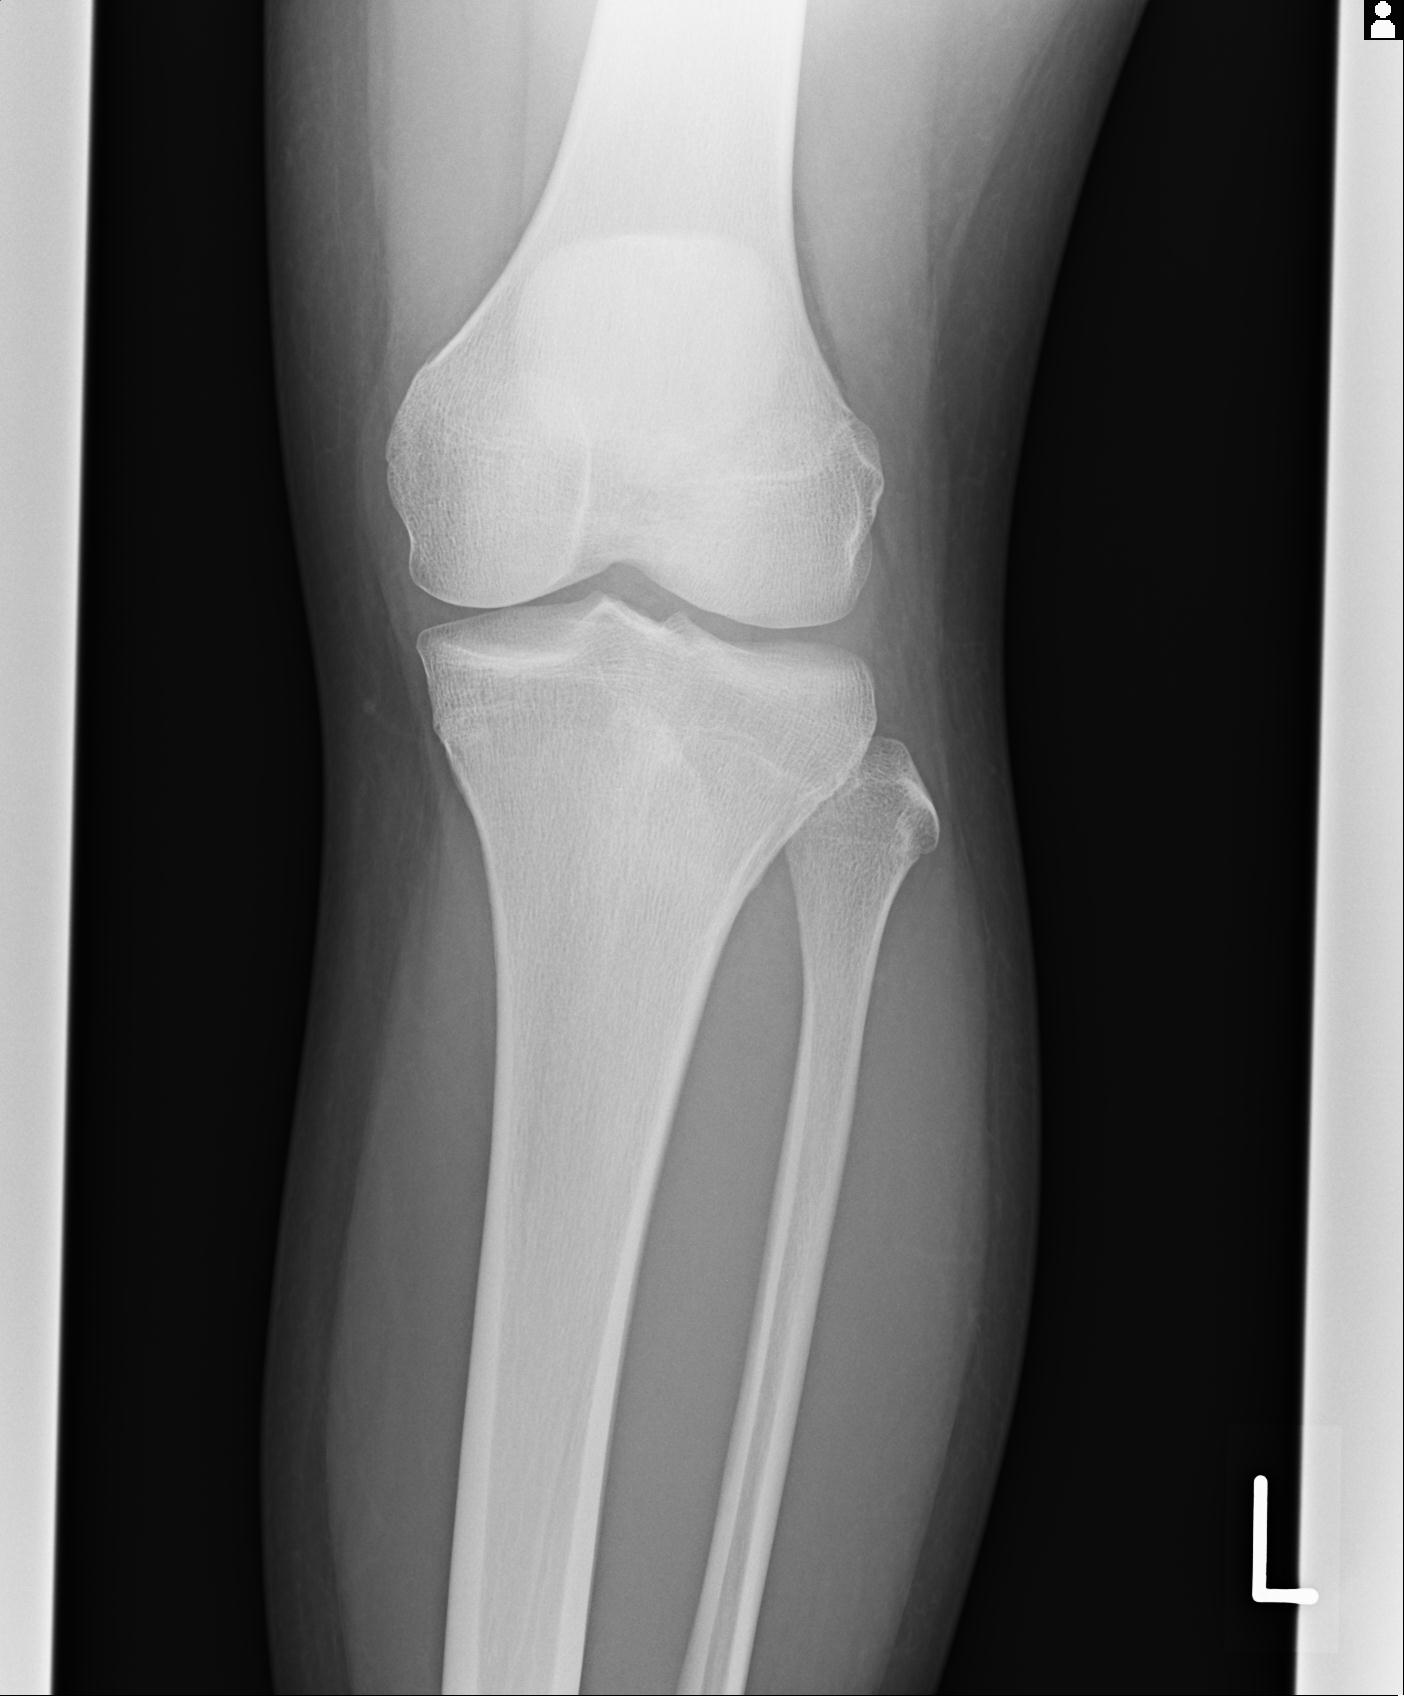

91983 11/16 左膝 2R 11/18 2R 55歳男性 脛骨骨切り術